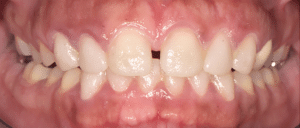

Dans notre cas clinique, il n’y avait pas de modification de la gencive à prévoir. Le mock-up est donc relativement réaliste. La patiente valide le diastème médian et le décalage des milieux (Fig.4).

Fig.4 : Essayage du mock-up.